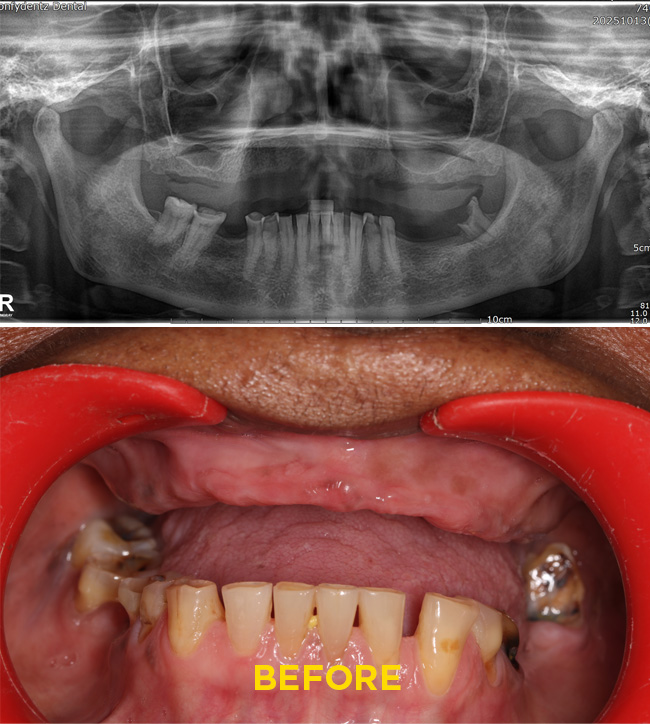

Case - 2